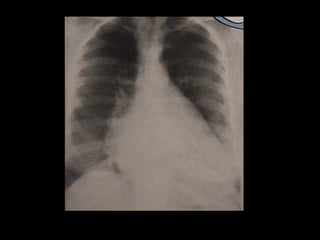

RADIOGRAFIA DE TORAX

1 – RADIOGRAFIA TORAX SIMPLES

– AUMENTO DO ATRIO ESQUERDO ,

-DILATAÇÃO DA ARTÉRIA PULMONAR

- CRESCIMENTO DE VD SE HP.

- CONGESTÃO PULMONAR

2- RADIOGRAFIA DE TORAX COM ESÔFAGO CONTRASTADO.

-VISUALIZAÇÃO DO 3 INVERTIDO NO EXAME OBLÍQUO

ANTERIOR ESQUERDA .

RADIOGRAFIA DE TORAX 1– RADIOGRAFIA TORAX SIMPLES – AUMENTO DO ATRIO ESQUERDO , -DILATAÇÃO DA ARTÉRIA PULMONAR - CRESCIMENTO DE VD SE HP. - CONGESTÃO PULMONAR 2- RADIOGRAFIA DE TORAX COM ESÔFAGO CONTRASTADO. -VISUALIZAÇÃO DO 3 INVERTIDO NO EXAME OBLÍQUO ANTERIOR ESQUERDA .